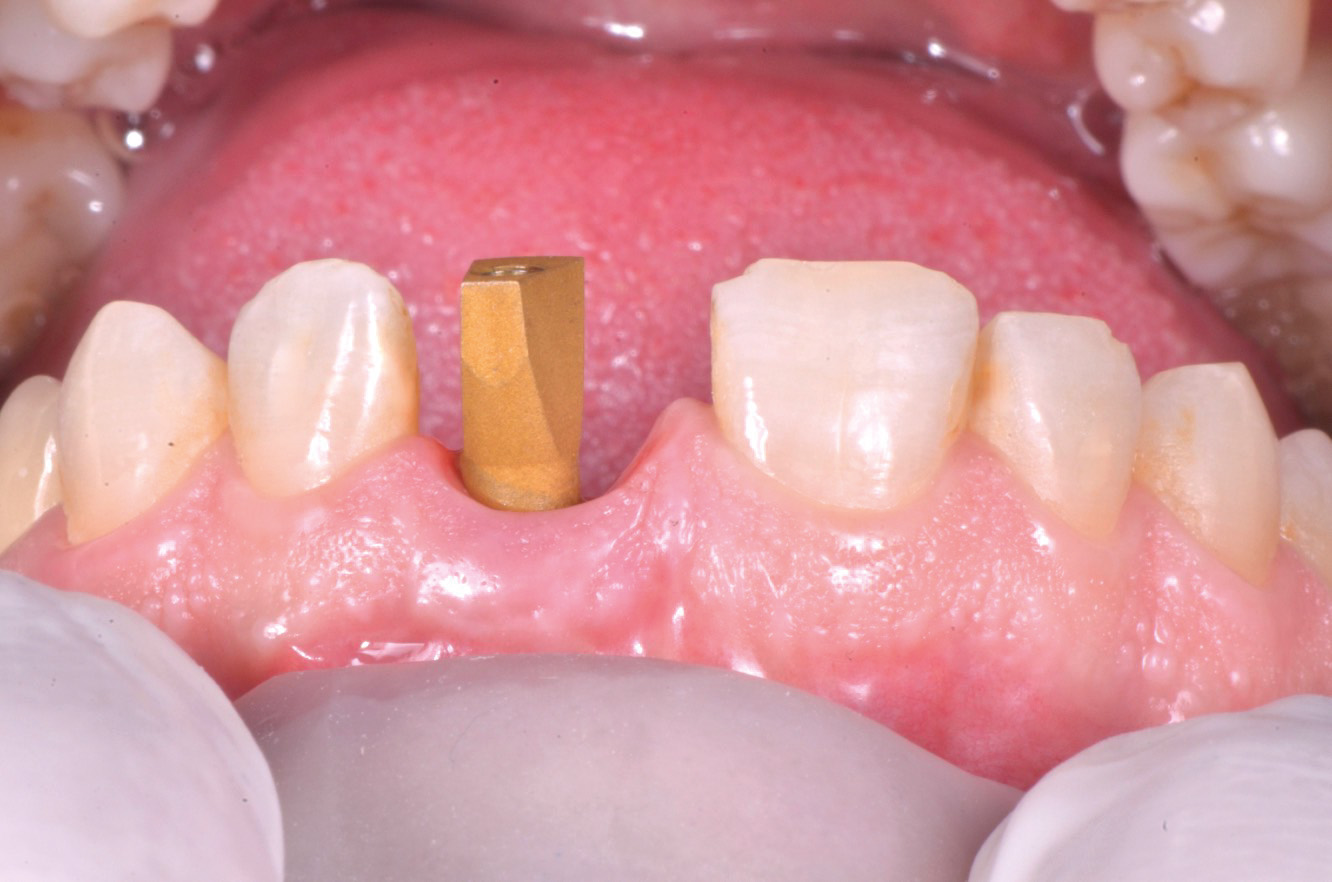

Seguendo le indicazioni del progetto chirurgico/protesico è stato posizionato un pilastro intermedio in titanio anodizzato (MIS Connect, MIS Implants ltd global, Bar Lev, Israele) con la tecnica del “one-abutment-one-time” con lo scopo di spiazzare la connessione protesica in una posizione più coronale (fig.9).

Un pilastro con vite dinamica è stato successivamente posizionato sul pilastro intermedio. Avendo optato per un inserimento post-estrattivo si è reso necessario compensare la “jumping distance” tra la parete vestibolare residua dell’alveolo e il corpo implantare e per questo è stato innestato osso bovino particolato deantigenato (Bioss, Gesitlich Biomaterials, Wollhousen, Svizzera). Successivamente sono stati gestiti i tessuti molli al fine di garantire un aspetto naturale del profilo esterno della cresta. Per questo è stato eseguito un prelievo epitelio-connettivale dal palato, successivamente de-epitelizzato, il quale è stato innestato “a busta” con un lembo a mezzo spessore con tecnica “a tunnel” sul versante vestibolare (fig.10,11).

Dal momento che l’impianto presentava un torque di inserimento superiore ai 40 N/cm2 è stato possibile proseguire con il trattamento come da progetto con la protesizzazione immediata. L’elemento provvisorio è stato fissato con del composito fluido al pilastro provvisorio grazie al posizionatore stampato 3D che ha permesso di mantenere l’esatta posizione progettata a software (fig.12).